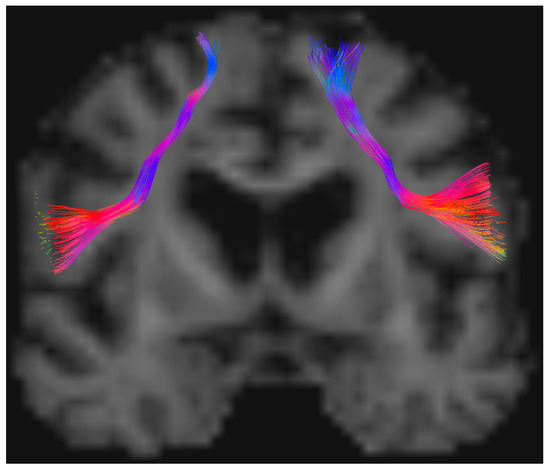

2.3. Imaging and Tractography Data

3.8. Illustrative Case